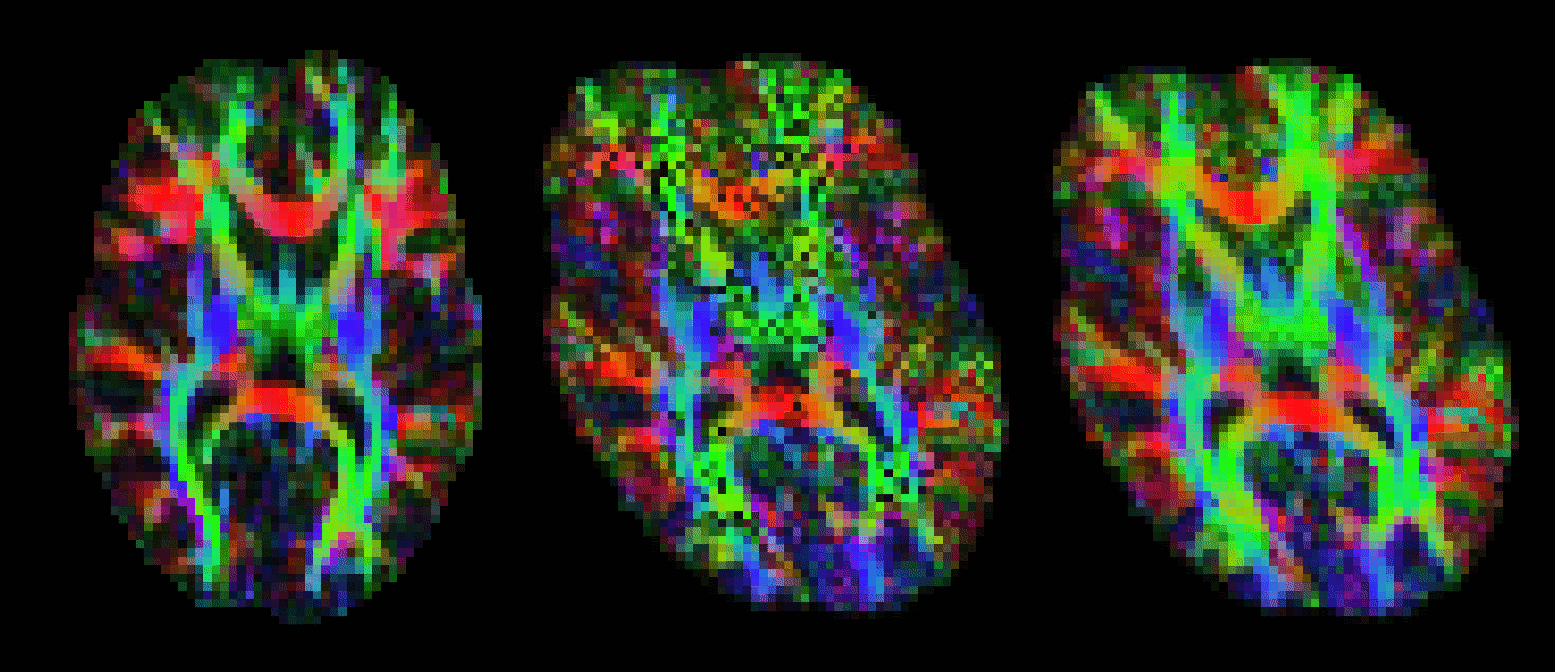

performs this operation for you. The image below shows the effect of applying vecreg

(right) to the V1 image on the left, compared to simply applying voxelwise transformation (e.g. using applyxfm4D) to the vectors (centre).